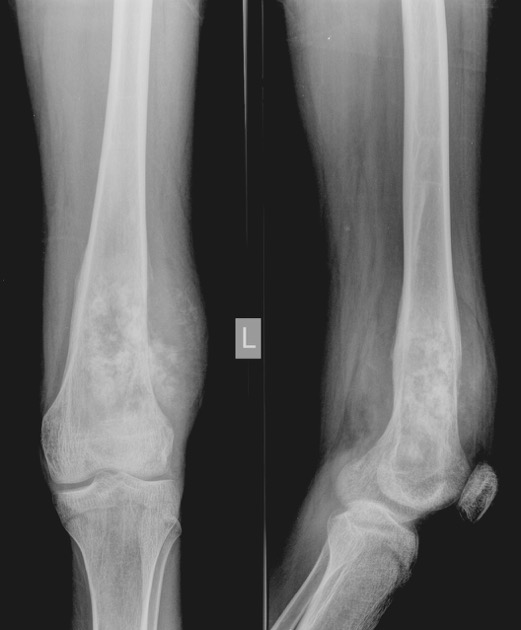

These are frontal and lateral radiographs of the lower 2/3 of the right femur and the knee joint of a mature skeleton. There is an expansile mass in the distal shaft of the femur with a soft tissue component on the lateral, anterior, and posterior aspects. It demonstrates areas of bone formation within. The zone of transition is wide. Fat planes are displaced by it and appear prominent, suggesting wasting of muscles. There is irregular periosteal reaction with Codman triangle present on the lateral aspect. No fracture. No other lesions. Overall findings are consistent with osteogenic sarcoma.